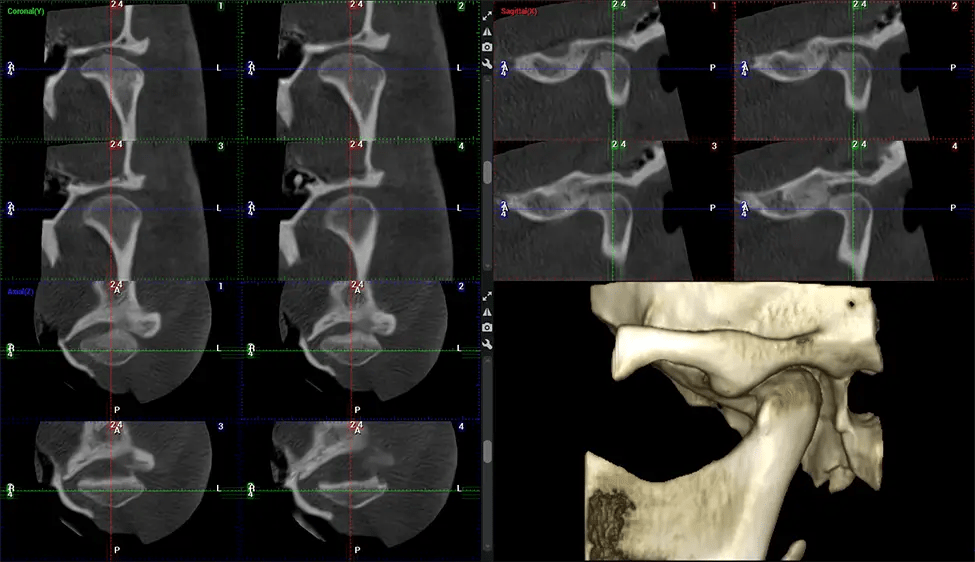

The patient is first positioned in the CBCT scanner, which typically consists of a rotating arm that houses the X-ray source and a detector. The patient’s head is immobilized to ensure accurate image capture. The X-ray source and detector rotate around the patient’s head, capturing various X-ray images from multiple angles. As the X-ray source rotates, it emits the cone-shaped X-ray beam towards the detector. The detector captures the X-ray images, which are then processed by the CBCT software.

After the scanning process, the captured X-ray images are processed by the CBCT software, which applies algorithms to reconstruct a detailed 3D image of the scanned area. The software compiles these individual X-ray images and creates a digital 3D representation of the patient’s anatomy. The reconstructed 3D CBCT image can be viewed and analyzed by the dentist or radiologist. This image can be manipulated, rotated, and zoomed in or out to examine specific structures and evaluate the patient’s condition.